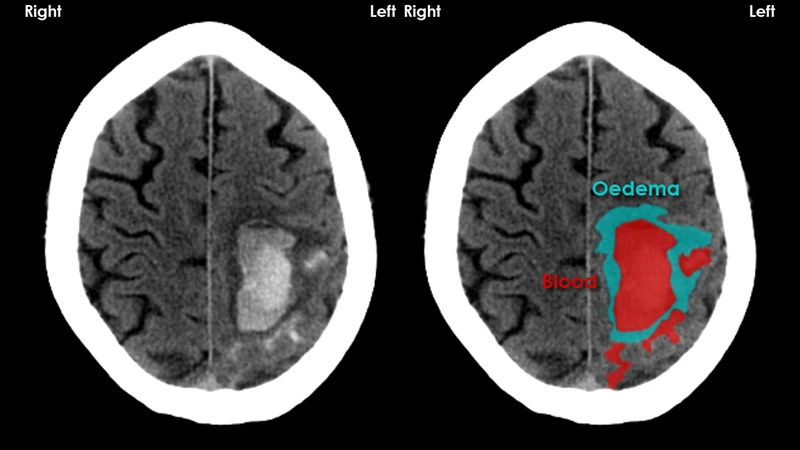

• Stroke: A non-contrast head CT is the primary tool for diagnosing a stroke. It can instantly determine if the stroke is caused by a bleed (hemorrhagic) or a clot (ischemic), which require completely different treatments.

A head CT image clearly showing a large, bright area of acute bleeding, a typical STAT finding.